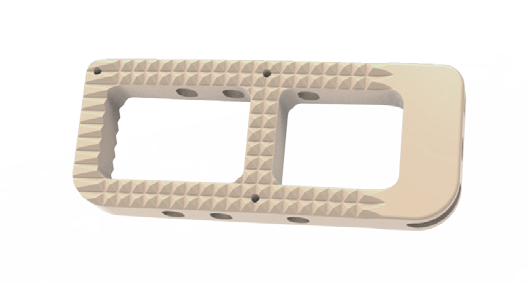

Sistema de cages para fusão intersomática, com diferentes modelos (Coales-P, C, M, T, L e Mesh), em PEEK, com marcadores de tântalo para melhor visualização e adesão óssea.

- Materiais: PEEK (ASTM F2026), Tântalo.

- Medidas: Diversas opções de altura, largura e ângulo de lordose.

- Usos principais: Fusão espinhal lombar e cervical, oferecendo estabilidade e suporte biomecânico.

- Tipo de produto: Cages intersomáticos para coluna vertebral.

- Compatibilidade: Compatível com técnicas de fusão TLIF, PLIF, ACIF, etc.

Design anatômico • Radiotransparente • Marcadores de tântalo para visualização • Reduz risco de subsistência